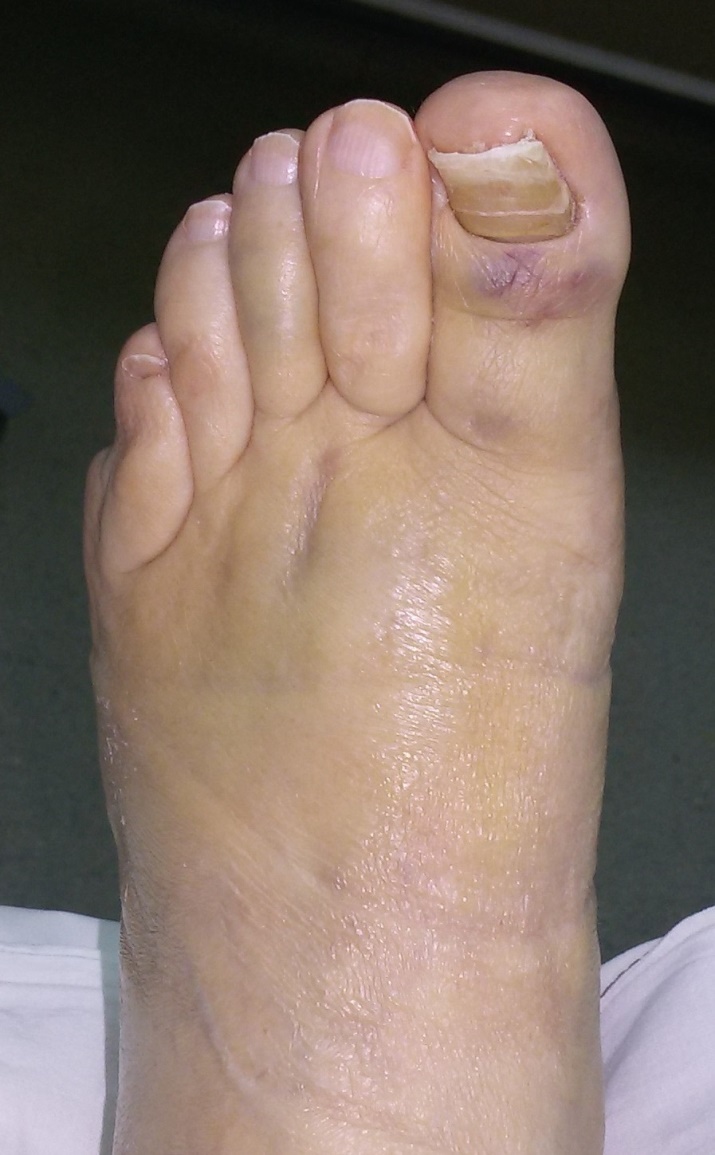

肖芯褌芯谐褉邪褎懈褟 褋褌芯褟 斜褘谢邪 锌褉懈褋谢邪薪邪 褔械褉械蟹 2 谐芯写邪 锌芯褋谢械 芯锌械褉邪褑懈泄. 袗 褔械褉械蟹  3

谐芯写邪, 锌褉芯褕械写褕懈屑 谢械褌芯屑, 锌邪褑懈械薪褌泻邪 褍锌邪谢邪 褋 谢械褋褌薪懈褑褘: 锌械褉懈锌褉芯褌械蟹薪褘泄 锌械褉械谢芯屑

斜械写褉邪. 效械褉械蟹 5 写薪械泄 锌褉懈械褏邪谢邪 芯锌械褉懈褉芯胁邪褌褜褋褟. 袨褌褋褞写邪 芯褌械泻 薪邪 褎芯褌芯 褋褌芯锌褘.